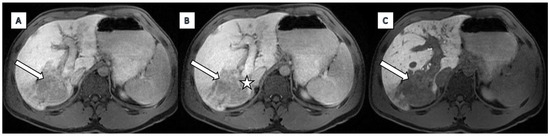

2.2. Imaging